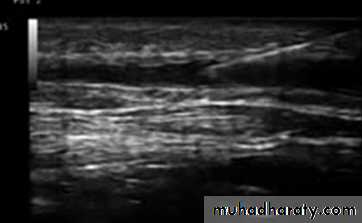

• Duplex Examination

DVT

Size of veins

Map out superficial veins

Locate the site of reflux

Find refluxing perforators

Duplex Anatomy

• Locate GSV Junction(FSJ)• Look for Mickey's

• Normal venous flow Look at valve

• Venous flow is opposite the artery